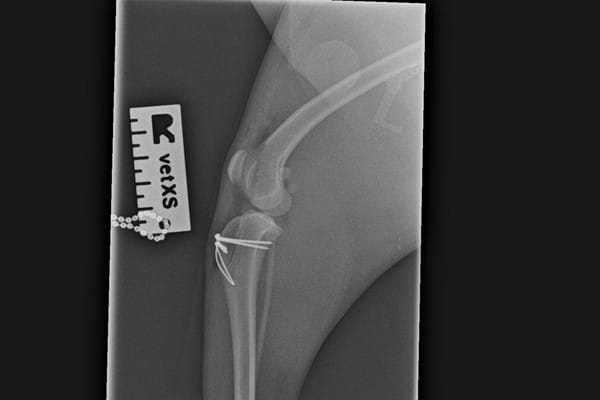

He discussed his findings with Sally and advised x-rays to further investigate the issue. The x-rays showed that Margaret had some inward deviation of her shin-bones which had happened whilst she was still growing and this was contributing to the laxity. Dr. Higson advised surgical correction for both of Margaret's hind legs, as the looseness of the kneecaps was causing discomfort and joint arthritis. Surgery was scheduled for the first leg and during the procedure, Dr. Higson deepened the groove the patella runs in and corrected the angulation of the top of the shin-bone.